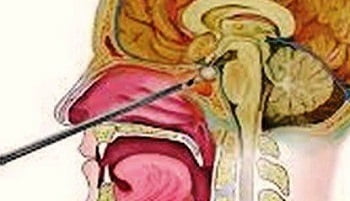

- Трансфеноидальный — через носовую полость.

Если диагностируют микроаденомы и макроаденомы, которые не оказывают серьезного влияния на окружающие ткани, хирургическое вмешательство проводят трансфеноидальным путем. Если опухоль достигает гигантских размеров (от 10 см в диаметре), рекомендовано исключительно транскраниальное удаление.

Трансфеноидальное удаление аденомы позволяется делать, когда опухоль ограничивается турецким седлом либо выходит за его пределы не более чем на 2 см. Выполняется в стационарных условиях после консультации с нейрохирургом. Введение эндоскопической аппаратуры производится под общим наркозом. Оптоволоконный эндоскоп вводят до передней черепной ямки сквозь правый носовой ход. Далее для освобождения доступа к области турецкого седла производится надрез стенки клиновидной кости. Аденому гипофиза иссекают и удаляют.

Все хирургические манипуляции выполняются под эндоскопом, увеличенное изображение текущего процесса выводится на монитор, благодаря чему нейрохирургу становится доступен широкий обзор операционного поля. Операция длится около двух-трех часов. В первые сутки после операции пациент уже может проявлять активность, а на 4 сутки — полностью выписан из больницы при отсутствии осложнений. В 95% случаях такой операции аденома гипофиза излечивается полностью.